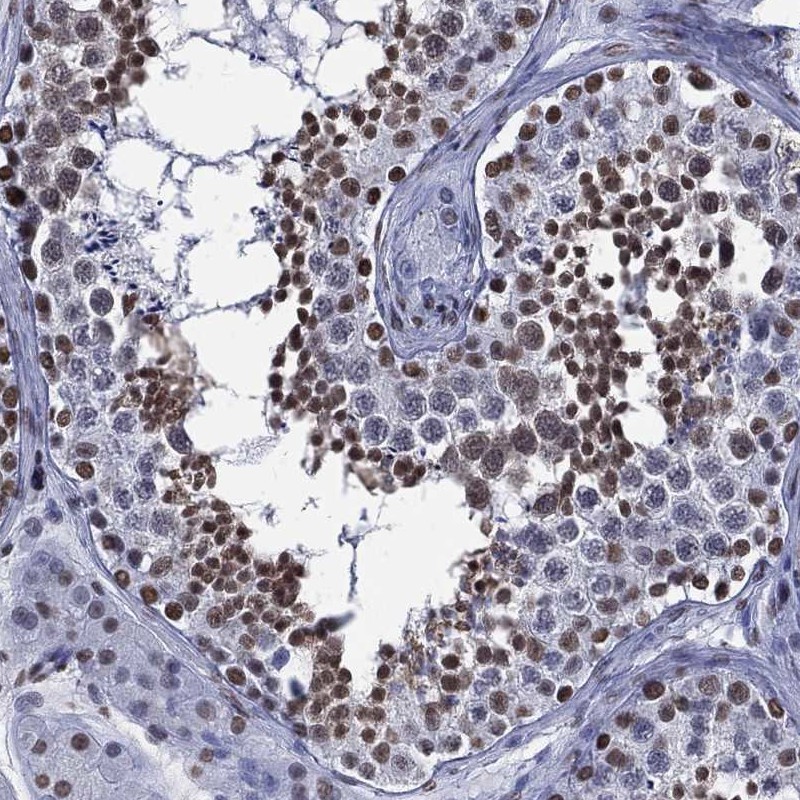

Immunohistochemical staining of human testis shows strong nuclear positivity in cells in seminiferous ducts.